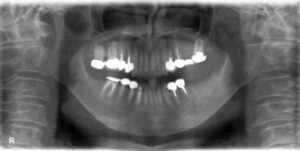

下顎大臼歯2本欠損症例

BEFORE AFTER 69歳女性/下2本欠損/インプラント埋込手術 【治療内容】 左下第一大臼歯、第二大臼歯が歯根の…